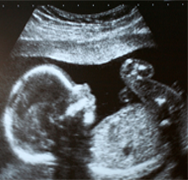

Babies with chromosomal defects most often suffer with both physical and mental handicap.It has now become possible to screen and diagnose these chromosomal abnormalities as early as the third month of pregnancy.

Every cell of our body has tiny structure called chromosomes. These chromosomes carry the genes that determine how we develop.Each cell in the body contains 46 chromosomes arranged in 23 pairs.One chromosome from each pair is inherited by the mother and the other from the father.Sometimes these pairs of chromosomes do not divide correctly and any defect in the number or stucture of chromosomes cause abnormalities in the unborn baby.Down's syndrome is one of the common chromosomal abnormalities.

A baby with Down's syndrome has an extra copy of chromosome number 21 in their cells. These babies unfortunaltely suffer from Physical (Heart defects,Gastrointestinal defects,abnormal facial features,hearing and eye problems,leukemia,thyroid problems,senile dementia etc) and mental handicap.

We are proud to introduce a full range of screening and diagnostic tests to detect the chromosomal abnormalities for the first time in coastal Andhra at our Andhra Hospitals, Vijayawada.This includes the consultation,tertiary level Ultrasound scan and detailed counselling by the highly qualified Maternal and Fetal Medicine Consultant Dr.Padma Paturi.